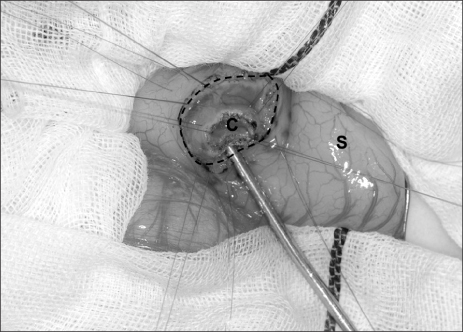

4] and the lumen was hypoechoic. A gastrografin swallow with upper gastrointestinal study demonstrated a mass obstructing the pyloric orifice. A small quantity of gastrografin passed around the perimeter of the lesion and entered the duodenum. Following fluid resuscitation and stabilization, an enteral digestive (ED) tube was inserted on day 7. Magnetic resonance cholangiopancreatography (MRCP) demonstrated that the cystic lesion was located in the pyloric orifice. However, T2-weighted sequences, obtained in the coronal plane did not reveal whether the fluid content of the lesion communicated with the bile duct or not. On day 22, body weight was 2,815 g and an operative exploration was undertaken. A laparotomy was performed through a transverse upper abdominal incision. No cyst was identified, but, an elastic mass was palpable at the pyloric orifice. Intraoperative endoscopy revealed a submucosal gastric lesion approximately 15 mm in size arising from the anterior and inferior surfaces of the pylorus (

Fig. 2). Intraoperative cholangiography documented no communication between the cystic lesion and the bile or pancreatic ducts. Gastrotomy was performed transversally over the antrum just proximal to the cyst, and the cyst was delivered in toto through the incision. The cyst was incised (

Fig. 2Endoscopic view showing the submucosal pyloric lesion approximately 15 mm in size.

Fig. 3Intraoperative findings of the duplication cyst. A transverse gastrotomy was performed to approach the cyst from inside the stomach. The cyst was incised and a mucosectomy was performed via a gastrotomy. C, cyst; S, stomach; broken line, transverse gastrotomy.